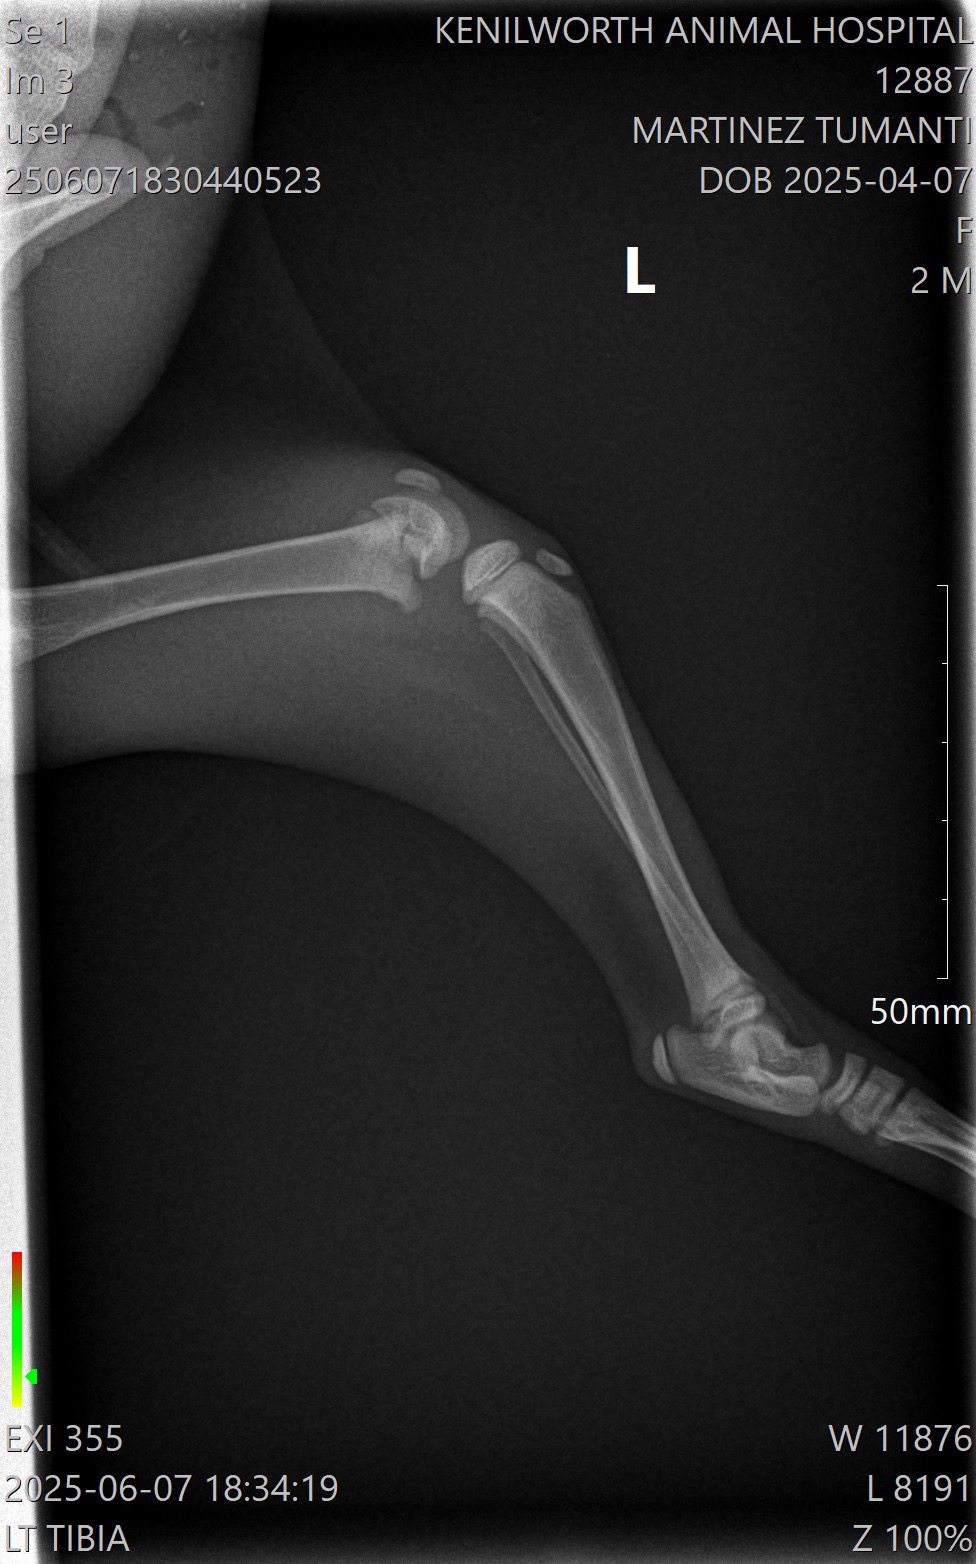

After many vet consults and visits, an orthopedic specialist at Eclipse Veterinary Hospital confirmed the dislocated hip and also found bilateral distal fractures in both of his hind legs. He will need surgical repair of the fractures, follow-up care, X-rays and pain management.